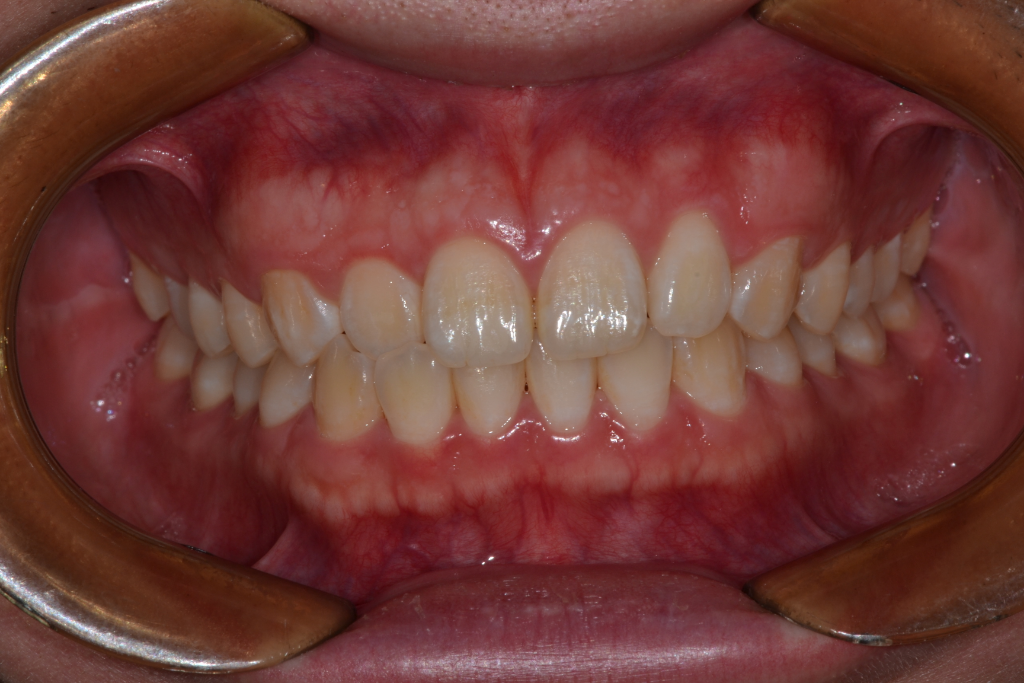

돌출입과 부정교합으로 인해

입이 벌어지게 되면 구호흡을하는 경우도 있습니다.